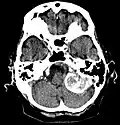

Kontrastmittel aufnehmendes Meningeom der linken Hemisphäre in der Computertomographie -

Großes Felsenbeinmeningeom in der Computertomographie -

Das bildgebende Verfahren der ersten Wahl ist beim Meningeom heute die Kernspintomografie, da dieses Verfahren den größten Weichteilkontrast besitzt und in typischen Fällen die sichere Diagnose eines Meningeoms ermöglicht. In T2-gewichteten Aufnahmen stellen sich verkalkte Meningeome im Gegensatz zu vielen anderen Tumoren als schwarze Masse (hypointens) dar, die dunkler als das umgebende Hirngewebe ist. Unverkalkte Meningeome können zur Umgebung isointens sein. Von anderen Tumoren unterscheiden sich Meningeome durch ihre Lage auf der Dura mater mit charakteristischen Ausläufern in die Dura (dural tails) und durch eine sehr intensive Kontrastmittelaufnahme. Die Computertomographie kann die Tumorverkalkungen sehr gut nachweisen. Konventionelles Röntgen und Angiographie haben heute nur noch eine untergeordnete Bedeutung.